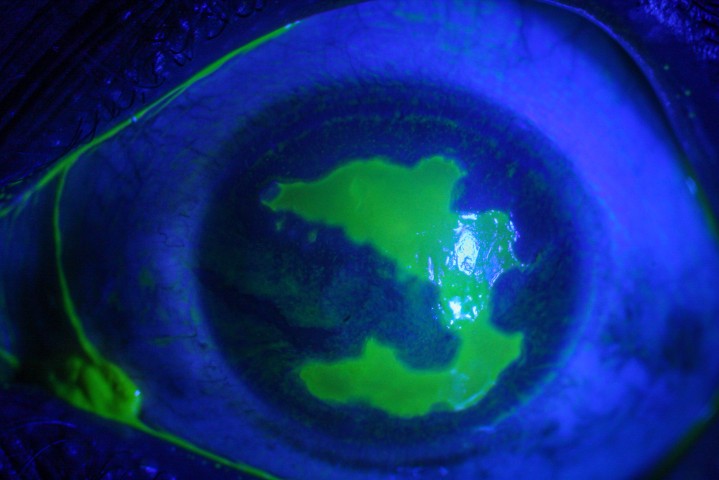

Patients under 40 years old represent a relatively straightforward group. The vast majority are myopes, although there will be a small number of relatively high hyperopes. Pre-operative refractive stability must be established (which usually means the minimum age for refractive surgery is around 20 years) and to reduce the risk of post-operative keratectasia (iatrogenic keratoconus) all patients require careful pre-operative screening with corneal topography/tomography, as well as an assessment of risk factors, such as eye rubbing and atopy. Dry eye must be assessed and treated vigorously pre-operatively as most laser techniques result in temporary dry eye, particularly in those with pre-existing dry eye.